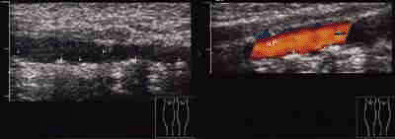

Links oben Halsschlagader, oben Beinarterien, links Nierengefäße

Unsere Praxis ist u.a. mit 4 hochwertigen Farbdopplersonographiegeräten ausgestattet,

Hiermit können Erkrankungen der Hals-, Hirn- sowie der Arm, - Nieren- und Beingefäße einfach, risikolos und mit hoher Zuverlässigkeit untersucht werden.